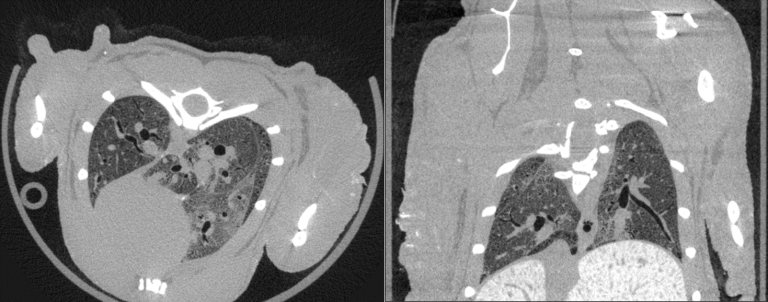

Milabs CT is capable of fast scanning and ultra-high-resolution scanning under low-dose X-rays, and the highest resolution can reach 10um.

- lung imaging